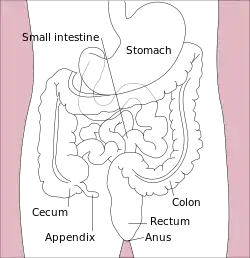

| Major parts of the |

| Gastrointestinal tract |

In humans, the anus (pl.: anuses or ani; from Latin ānus, "ring", "circle")[1][2] is the external opening of the rectum, located inside the intergluteal cleft and separated from the genitals by the perineum. Two sphincters control the exit of feces from the body during an act of defecation, which is the primary function of the anus. These are the internal anal sphincter and the external anal sphincter, which are circular muscles that normally maintain constriction of the orifice and which relaxes as required by normal physiological functioning. The inner sphincter is involuntary and the outer is voluntary. It is located behind the perineum which is located behind the vulva or scrotum.

Structure

The anus is the final part of the gastrointestinal tract, and directly continues from the rectum, passing through the pelvic floor. The top and bottom of the anus are surrounded by the internal and external anal sphincters, two muscular rings which control defecation.[6]: 397 The anus is surrounded in its length by folds called anal valves, which converge at a line known as the pectinate line. This represents the point of transition between the hindgut and the ectoderm in the embryo. Below this point, the mucosa of the internal anus becomes skin.[6] : 397 The pectinate line is also the division between the internal and external anus.